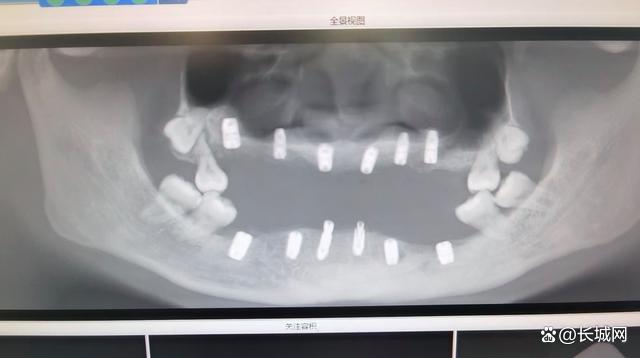

△CT结果显示,朱女士全口除了没有咀嚼功能的四颗智齿外,只剩4颗牙齿